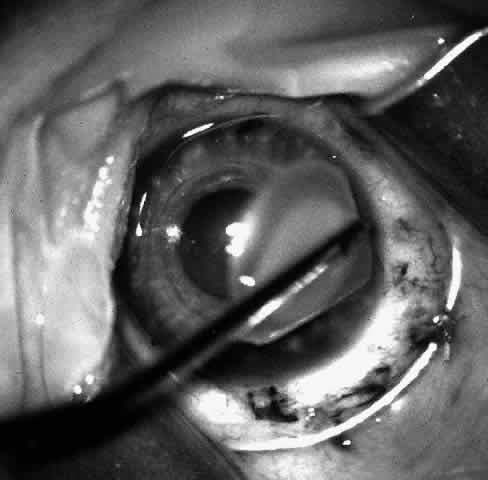

Next, an angled lamellar dissector such as one would use to dissect a trabeculectomy flap is used to create a 1-mm lamellar pocket in the peripheral direction for 360° around the cornea at the base of the trephined incision. In the past a small strip of cornea was excised centrally from the inner aspect of the trephine incision. This keratectomy has been found unnecessary and the procedure may be more easily reversed without the keratectomy. Then the tissue lens is draped over the cornea stroma-side-down and centered on the annular incision (Fig. 9).

Fig. 9. Hydrated lens is placed on the front of the cornea.